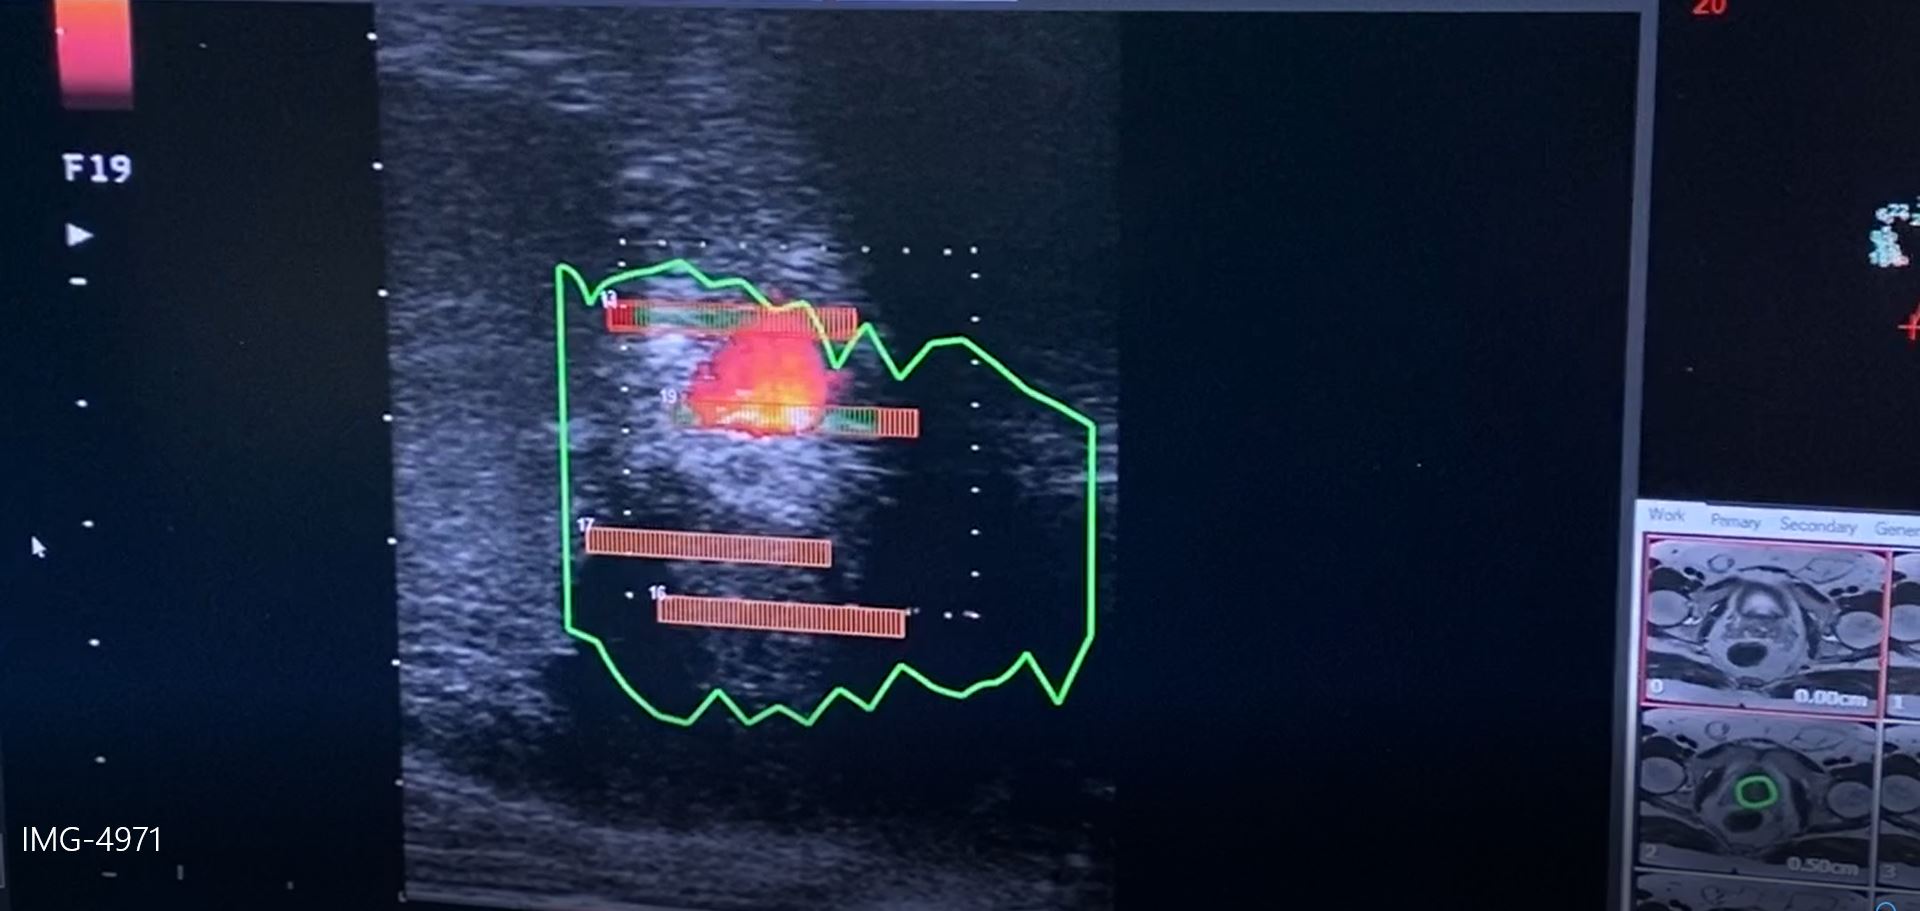

Εγώ με την ομάδα μου ακολουθούμε απο το 2016-που για πρώτη φορά στην Ελλάδα ξεκινήσαμε αυτού του τύπου την θεραπεία και κάθε χρόνο παρουσίαζουμε στα διεθνή συνέδρια τα παοτελέσματα μας ,έχοντας πλέον μία αξιοπρόσεκτη εμπειρία-ένα σύνολο αυστηρών προτύπων στούς άνδρες που πρόκειται να λάβουν εστιακή θεραπεία. Αυτό περιλαμβάνει μια ενδελεχή αξιολόγηση δια μέσω πολυπαραμετρικής μαγνητικής τομογραφίας προστάτη και υβριδικών διαπερινεϊκών βιοψιών , το βαθμό κακοήθειας Gleason απο τις βιοψίες ,το PSA,την ηλικία ,τις συνοδές παθήσεις κ.α. για να επιβεβαιωθεί ότι ο όγκος είναι μικρός και εντοπισμένος και ότι μια πιο εκτεταμένη θεραπεία δεν είναι απαραίτητη όπως είναι π.χ. η χειρουργική ή η ακτινοθεραπεία ..png)

Τα είδη εστιακής θεραπείας που προσφέρουμε στους ασθενείς μας -και μόνο εφ’όσον πληρούν τα κριτήρια ένταξης στη κλινική μας μελέτη- είναι: